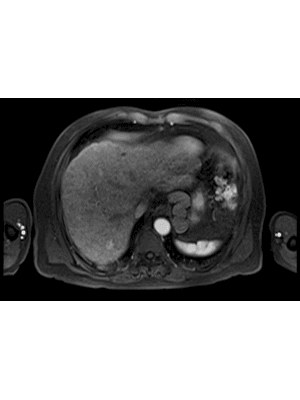

The diagnostic uses of ultrasound in liver cancer are well established. Ultrasound plays a key role in surveillance, biopsy and, increasingly, in characterisation, with the use of contrast-enhanced ultrasound (CEUS). The treatment of liver cancer using ultrasound is perhaps less well appreciated. Ultrasound is used in the treatment of liver cancer in two ways: firstly and most commonly, to guide needle mediated ablative therapies; secondly, it can be used as treatment with high intensity focused ultrasound (HIFU) and more recently cavitation-based treatments (histotripsy).